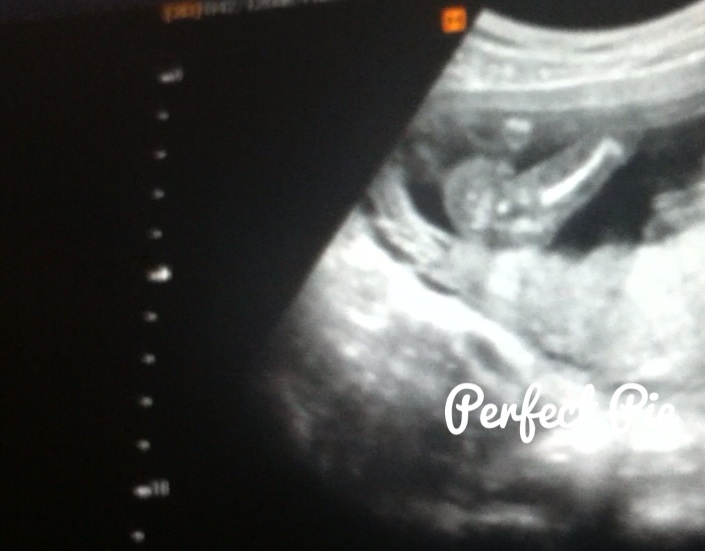

Attachment 19527Attachment 19528At my NT scan at 13 weeks (baby measured 14 weeks 1 day) the tech said if she had to bet she would say it is a girl. Yesterday I had a scan at 16 weeks(not sure where baby is measuring) with my ob he said he's not an expert but that he agrees with the tech that baby is a girl and that we can tell family just not announce on facebook(not a problem for me :) ). I'm still nervous that our little girl is actually a boy that's why I would love some more opinions/guesses from you all. Thanks!